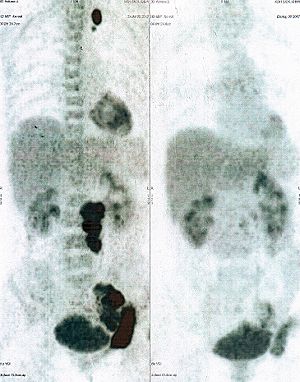

Below are some of the cases, from more than 80 cases we have treated so far with good results. When reading the PET/CT scans, the picture on the left is before treatment, and the picture on the right is after treatment. The intensity of black represents the activity of the cancer, but some black areas are not cancer: brain, heart, radioactive urine in bladder. For the heart, the intensity of black depends on the number of hours of fasting: if more than 10 hours, the heart is not even black, but if fasting is less than 6 hours, it is very black. The intensity of black in the brain can be variable in different scans depending on the brain activity at the time of the scan. The intensity of black in the radioactive urine can also be variable due to the hydration of patients and the time of injection of diuretic.

CASE NO: 28 (MASSIVE LIVER METASTASES)

A 50+ woman is very weak and bedridden, with massive liver metastases of unknown origin. After a few treatment, the cancer in the liver has shrunk by more than half, and the women can walk and feels much better. Treatment is continuing. This case illustrates again that it is not necessary to know the histology of the cancer before starting treatment.

CASE NO: 29 (OVARIAN CANCER)

A 40+ women has recurrent ovarian cancer in the lower abdomen, resistant to chemotherapy. After a few treatment, most of the cancer went into remission with only a small bit left. Treatment is continuing.